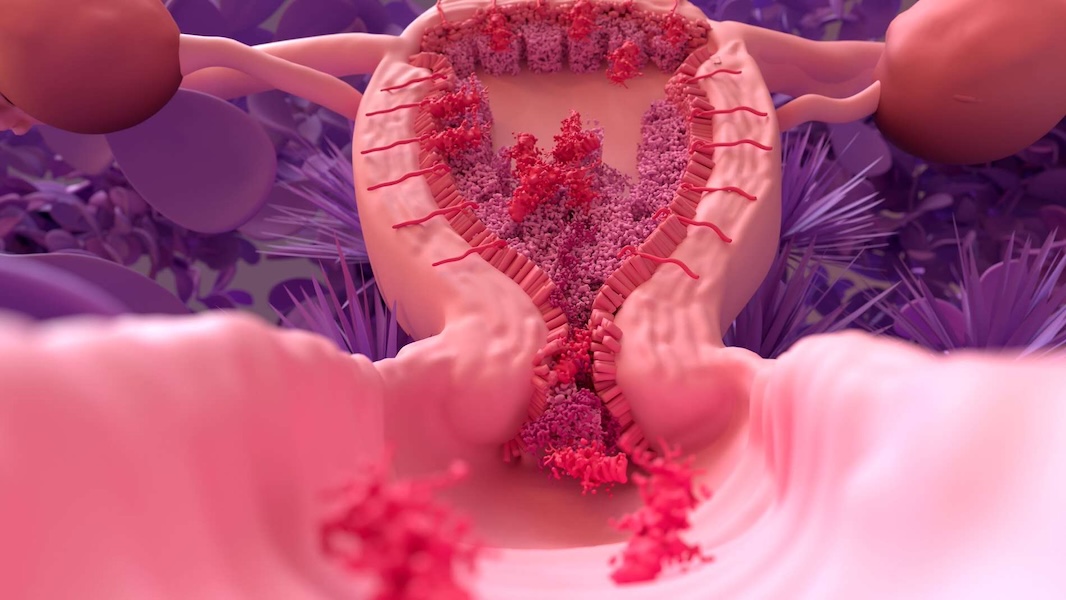

La causa más frecuente es una lesión del endometrio (revestimiento interno del útero), generalmente asociada a:

- Legrados uterinos postparto o postaborto

- Procedimientos ginecológicos previos

- Cirugías uterinas

- Infecciones uterinas severas

- Retención de restos ovulares o placentarios

Estas agresiones pueden generar una cicatrización anormal, dando origen a las adherencias.